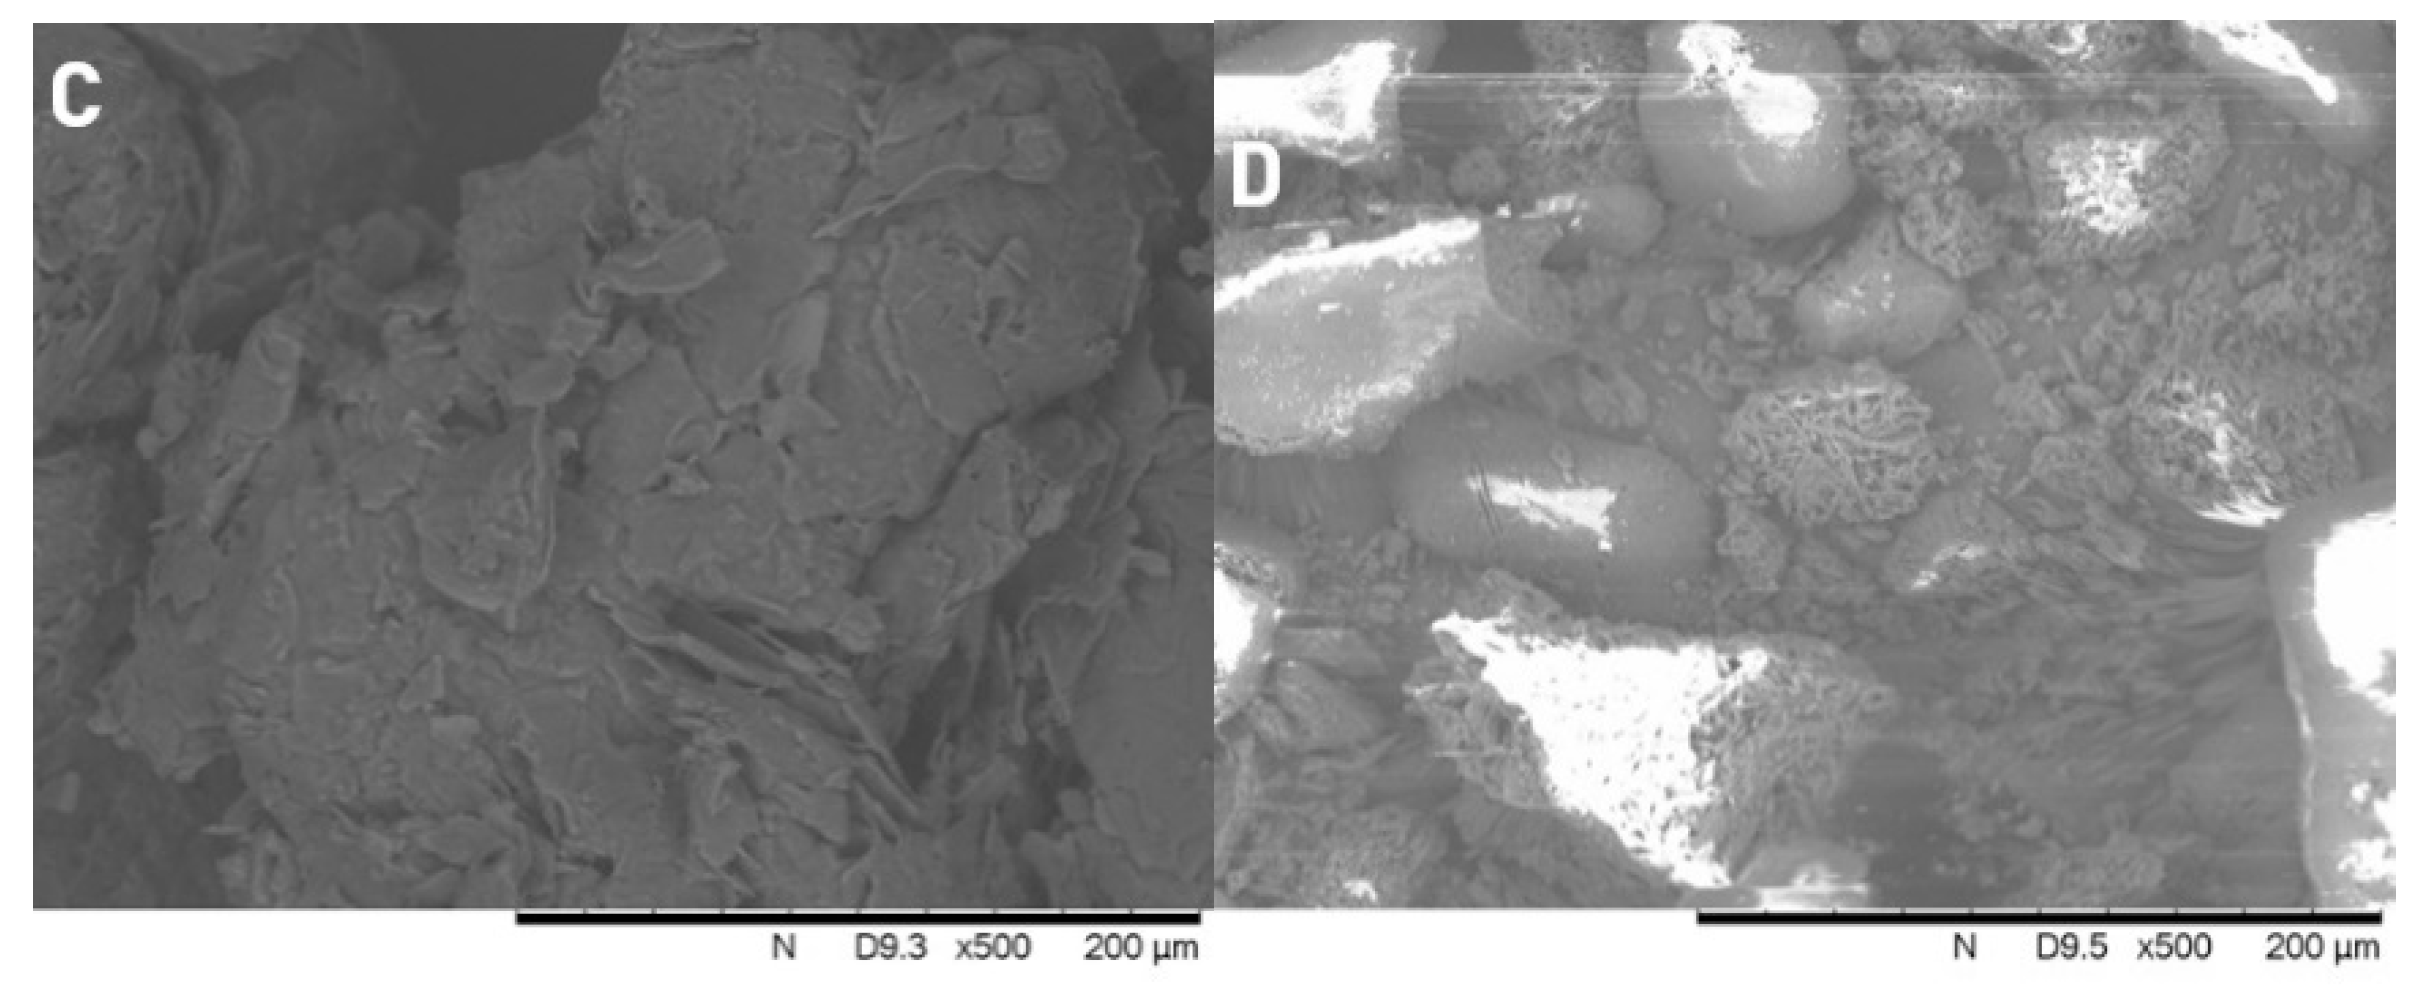

3.4. Scanning Electron Microscopy (SEM)